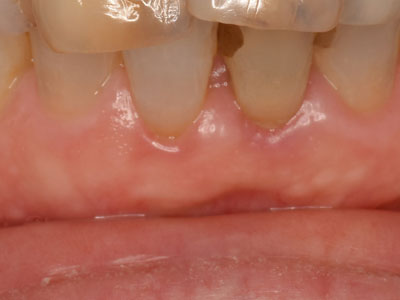

歯周形成外科

結合組織移植術

歯周病などによって歯肉が下がってしまった場合に行う処置です。歯肉が下がると歯が伸びたように見え、見た目が悪いだけでなく、むし歯になりやすかったり、知覚過敏になったりします。そこで上顎の裏側から取った結合組織を、歯肉が足りない部位の上皮と骨膜の間に移植する方法です。露出した歯根を覆ったり、歯肉の厚みを確保します。

術前

歯肉が一部下がってしまっている

術直後

口蓋から採取した組織を移植

術後

歯肉が回復した状態